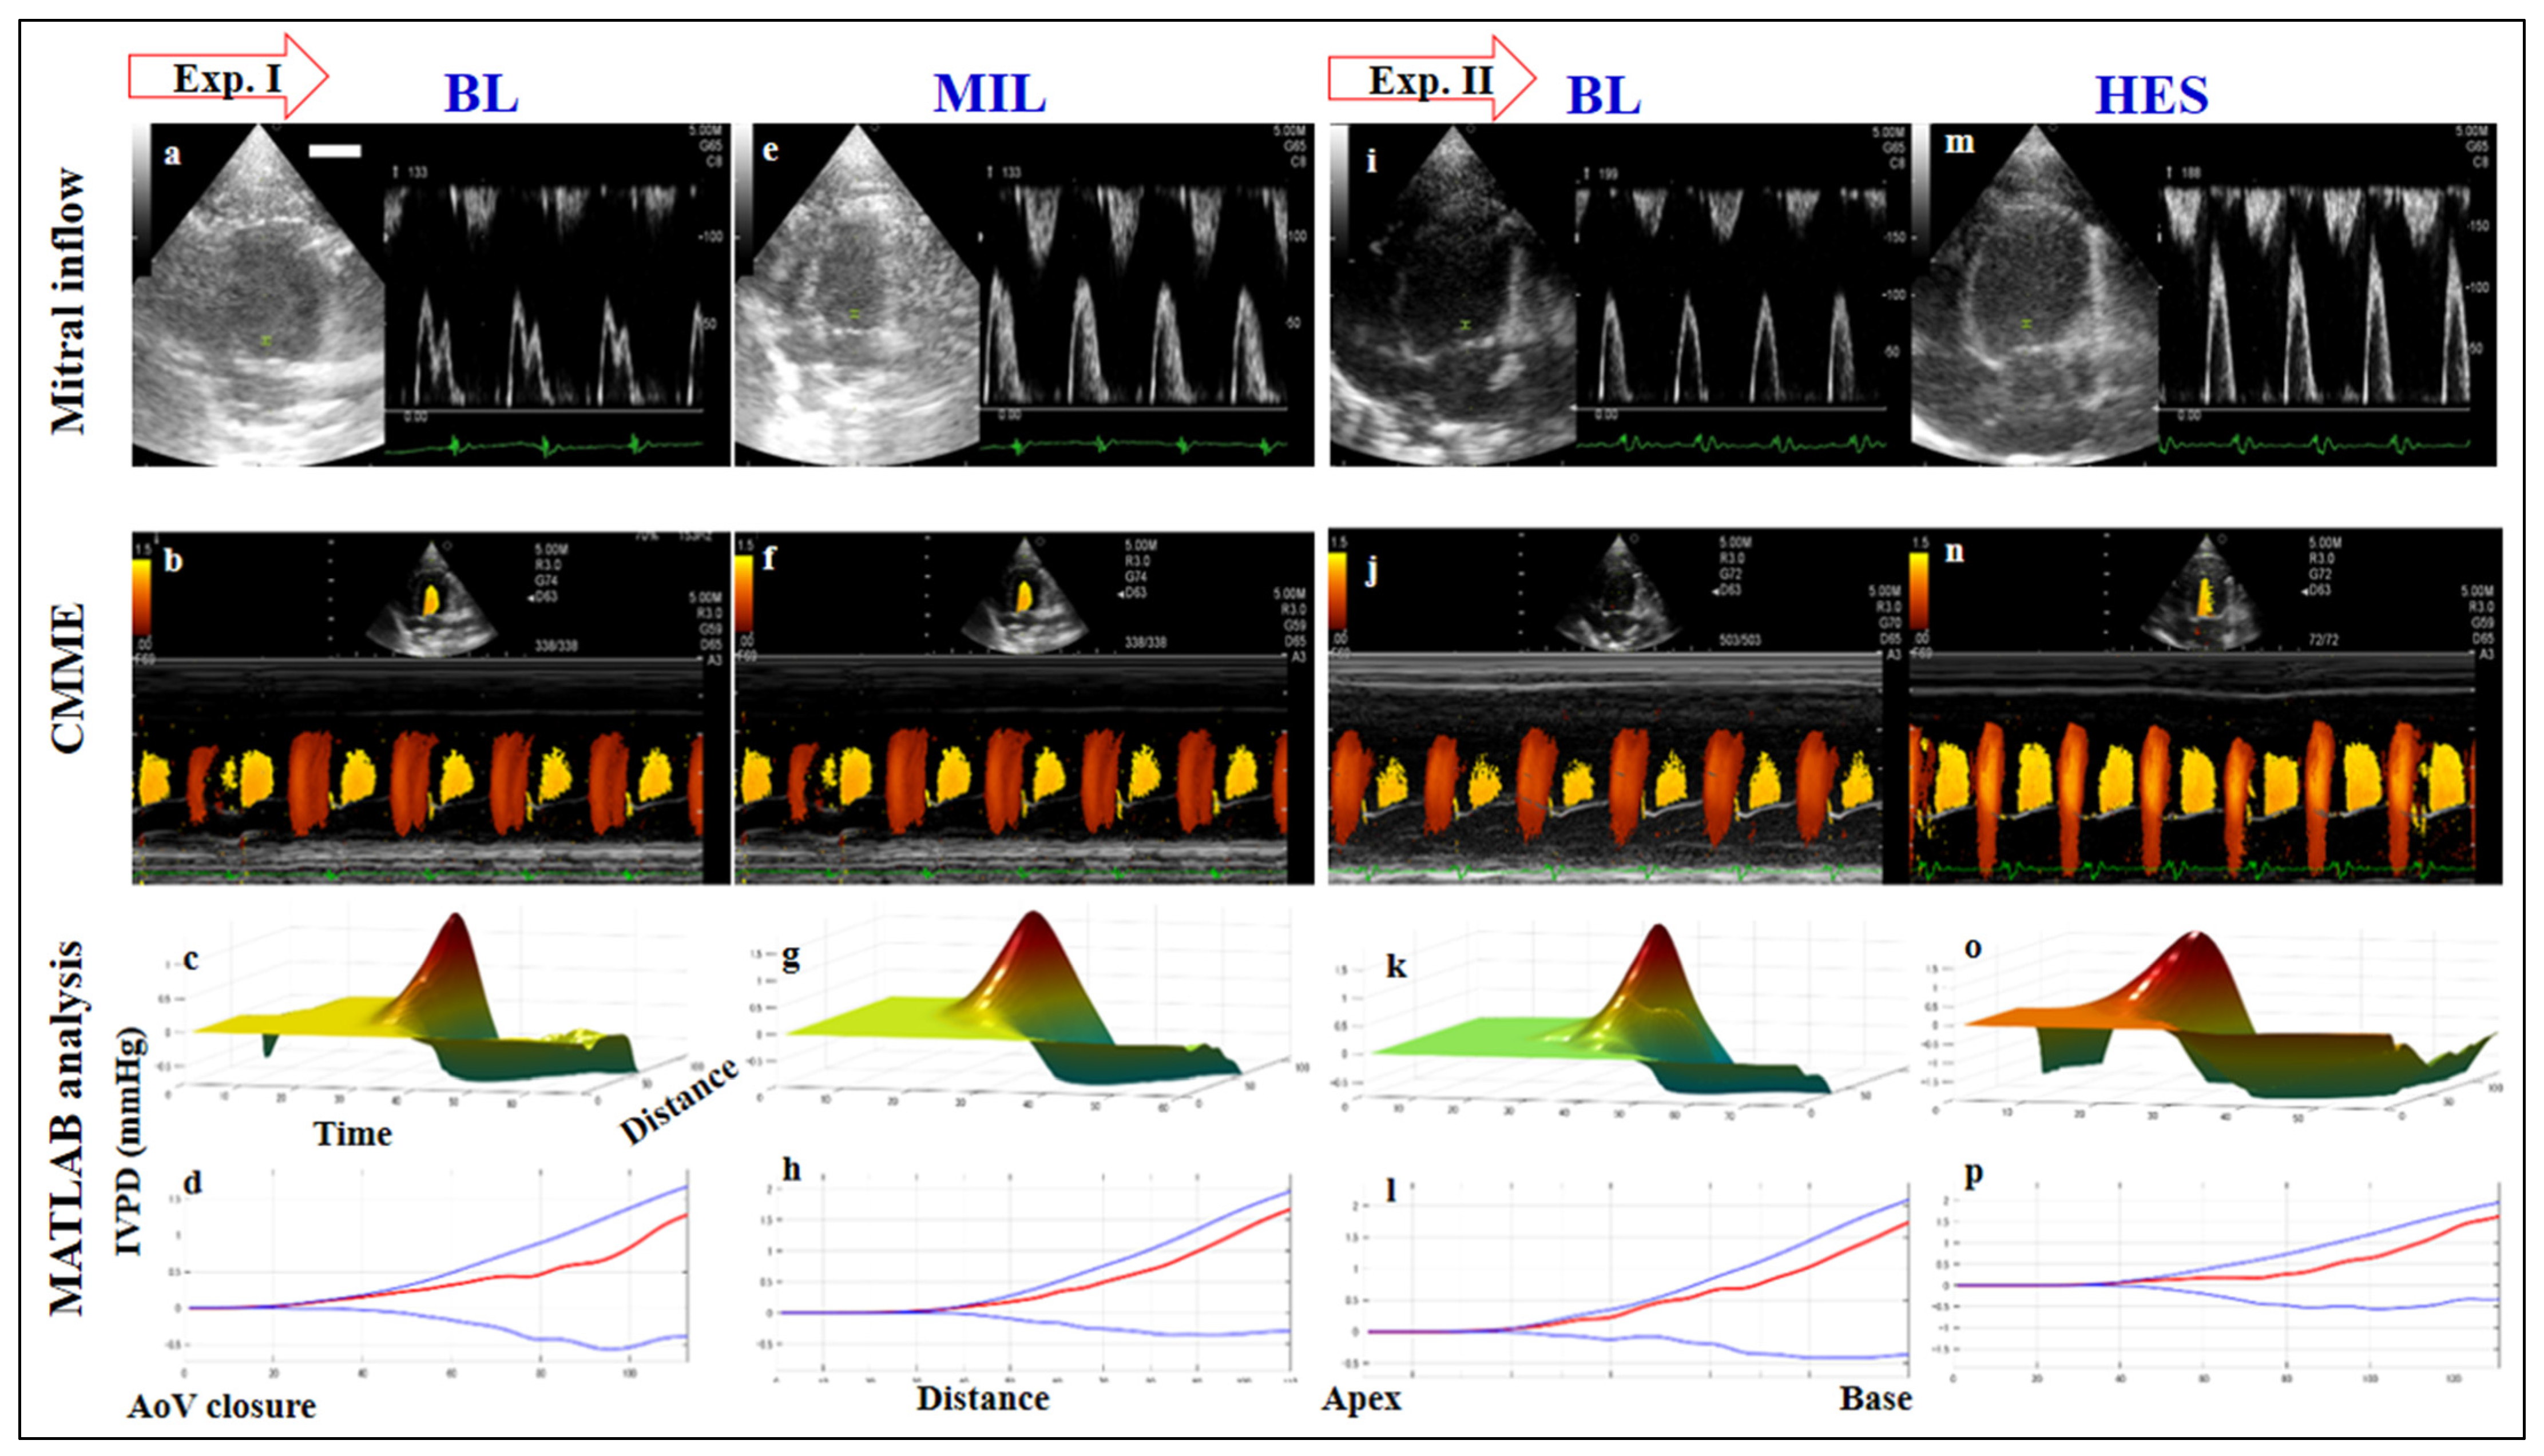

2.4. Color M-Mode Echocardiography (CMME)

3.3. Color M-Mode Echocardiography

3.3.1. Effect of Loading Condition on IVPD

3.3.2. Effect of Loading Condition on IVPG